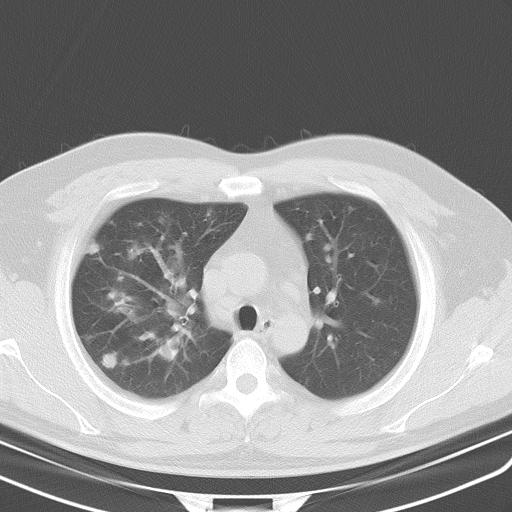

标题: CT13304:胸部多发结节影,少见,请会诊!!!! [打印本页]

标题: CT13304:胸部多发结节影,少见,请会诊!!!!

患者男性 35 主因发热咳嗽四天,血象不高,心肺听诊未见异常,无其它病史及传染病接触史。

双肺多发散在结节影,部分边界不清,延支气管分布;纵隔内多发小结节(淋巴结)影...

考虑

1.双肺转移ca及纵隔淋巴结转移;

2.特殊类型感染(霉菌)?

3.韦氏肉芽肿?

肺内多发大小不等结节影,以外周为著,纵隔见多个淋巴结肿大;结果病人,35岁,有发烧咳嗽等病史,首先考虑血源性肺脓肿可能性大,建议积极抗炎治疗后复查,除外转移瘤或韦格氏肉芽肿.